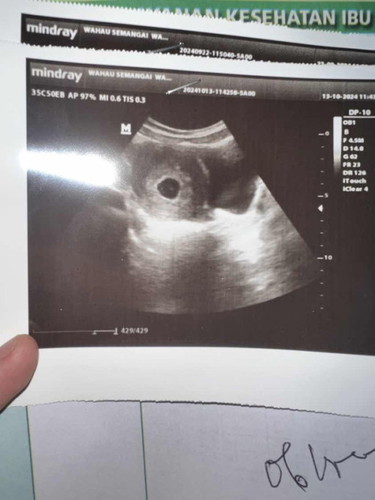

#SeriusTanya #ingintahu #firstmom mohon doanya bunda” semua🙏🏻 sebelumnya memang sering flek yg pudar tdk terlalu kelihatan nah baru aja tdi fleknya lumayan bnyakk warna coklat kemerahan. minggu lalu sdh usg kantung dan janin alhamdulillah sdh ada untuk djj blm disuruh balik bulan depan. hasil usg dokter bilang usianya beda 3 mingguan lebih dari hpht dan terancam keguguran. karna flek yg lumayan bnyk ini saya konsultasi lgi ke dokter lewat chat dan disarankan usg 2 minggu kemuadian. saya cuma diresepin asam folat sm anti pendarahn dari dokter tdk ada penguat. smoga di usg selanjutnya janin saya baik” sj sdh ada djj dan berkembang dgn sehat Aamiin ya Allah semuanya sy pasrahkan kpdMu🤲🏻